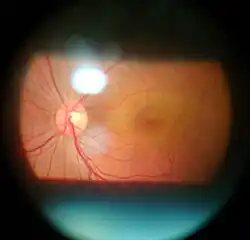

In ophthalmology and optometry, a slit lamp is an instrument consisting of a high-intensity light source that can be focused to shine a thin sheet of light into the eye. It is used in conjunction with a biomicroscope. The lamp facilitates an examination of the anterior segment and posterior segment of the human eye, which includes the eyelid, sclera, conjunctiva, iris, natural crystalline lens, and cornea. The binocular slit-lamp examination provides a stereoscopic magnified view of the eye structures in detail, enabling anatomical diagnoses to be made for a variety of eye conditions. A second, hand-held lens is used to examine the retina.

Fundus observation is generally performed via ophthalmoscopy, where the observer (fundus camera or observing eye) is focused to infinity, which brings the subject's fundus into focus due to the refractive power of the subject's optical media. In contrast, the microscope in slit lamp biomicroscopy is focused to the anterior segments of the eye, such that direct observation of the fundus is impossible due to the subject's refractive power. However, with the use of auxiliary optics, the fundus can be brought within the focusing range of the microscope. These optics usually take the form of a lens placed on or near the subject's cornea, which range in optical properties and practical application.[19]